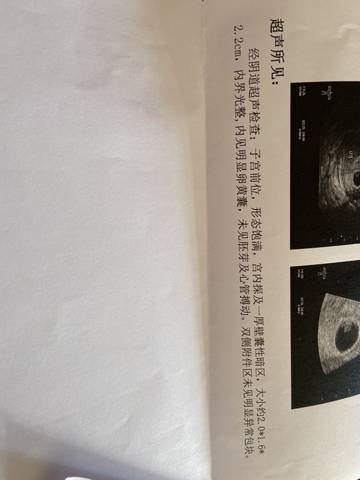

怀孕6+5天,孕酮17.2ng/ml绒毛膜促性腺激素36989.2mIu/ml,B超内见明显卵黄囊,未见胚芽及心管搏动,就属于正常还是?

journal_insert_pic_1674751280